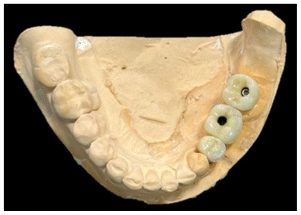

The maxilary and mandible were scanned with a Medit I500 Scanner, the lower scanning of the distal extensión of the mandible was difficult to obtain because of the mobility of the mucosa and the scanner lost the track. Conventional impressions were taken and an analog wax-up was made that gave us the ideal occlusion based on the antagonist, in the same way a digital wax made base don the analogic wax up, then the mandible and upper jaw were printed in stereolithography (Figs. 22, 23).

When analyzing the case in conjunction with the impression, the sterolithography, the digital scanning, waxing and position og the implants in the CT scan, it was observed that the ideal center of the crowns would be outside the prosthetic center, because the bone formed was not thick enough, the placement of the implants would have to be in a crossbite and try to correct it with milled and angled attachments. with screw-retained crowns to leave a better occlusion (Figs. 23, 24).

A surgical guide based in the analysis was elaborated for the the surgery. Three implants were placed in the new bone formation of the mandible, one in the premolar and two in the molars, Nobel Replace conical connection implants of 35 × 10 mm, 4.3 × 8 mm, 35 × 11.5 mm were used, a two-phase protocol was chosen, (Figs. 25, 26, 27).